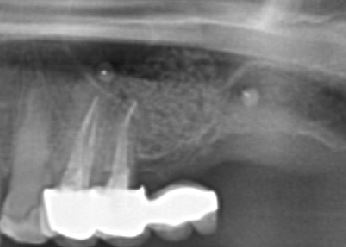

Le sinus lift (accès par voie latérale) : lorsqu’il manque de l’os en arrière du maxillaire supérieur, on accède au sinus par une paroi latérale et on le comble avec nos matériaux. Cela augmente la hauteur osseuse disponible.